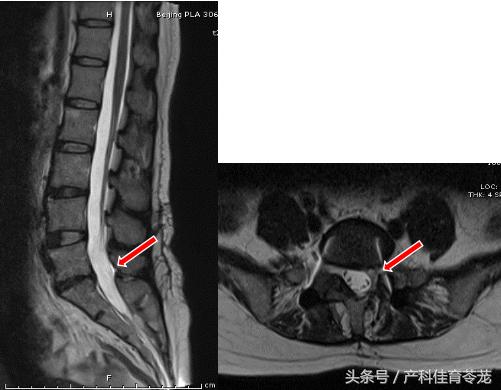

术后症状完全缓解,3天后下地活动,1个月就恢复上班,半年后复查核磁提示髓核突出消失。